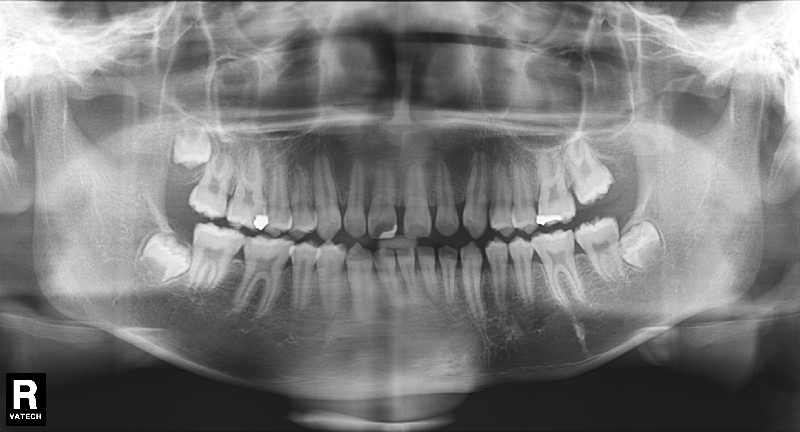

치료 전 사진입니다.